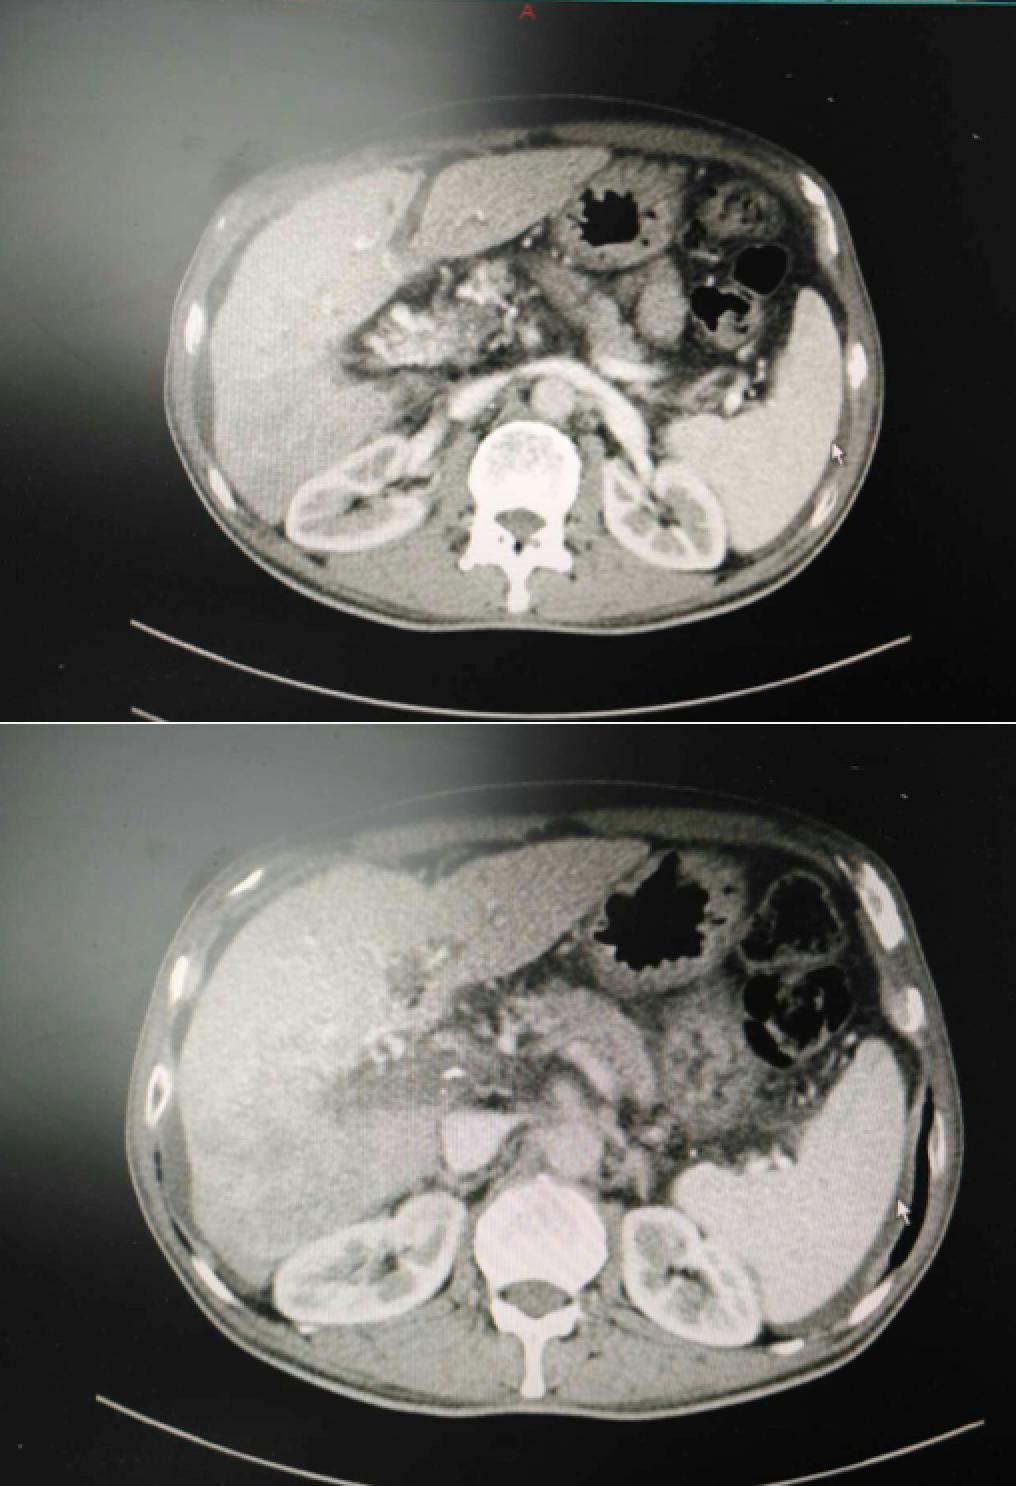

患者因纳差、烧心、腹痛、腹胀2月,于2016-01-17在某县人民医院行腹部CT示肝癌并门脉癌栓形成。分别于2016-01-22、2016-02-19于某市医院行两次TACE术(具体不详)。患者介入术后规律服用抗乙肝病毒、保肝、提高免疫力等药物治疗。2016-02-03至2016-04-30在某省立医院行5周期CIK免疫治疗。2016-05-18至2016-05-25于我院行射波刀治疗门静脉癌栓,具体放疗计划为:42Gy/7F。2016-06-24在我院行肝右动脉化疗栓塞术+肝右动脉灌注化疗术+间接门脉灌注化疗术,术中化疗总量,吡柔比星2mg、顺铂12mg、氟尿嘧啶250mg。分别于2016-05-10、2016-05-27、2016-06-13、2016-07-01、2016-07-27、2016-08-22、2016-09-19、2016-10-07、2016-10-19、2016-11-18、2016-12-18、2017-02-18行12周期免疫治疗。自2016-05-12起患者间断口服靶向药物阿帕替尼250-500mg/d,血压维持在220-130/95-70mmHg,血压升高期间伴上腹部不适,左侧为著,并向腰背部放射,偶尔反酸、烧心,剑突下疼痛,口服抑酸剂或进食后缓解,临床诊断为十二指肠溃疡,目前口服奥美拉唑、马来酸依那普利、氢氯噻嗪等药物对症降压。2017-03-02于我院行第二次肝右动脉化疗栓塞术+肝右动脉灌注化疗术+间接门脉造影术+肠系膜上动脉灌注化疗术。术中化疗总量,洛铂10mg、氟尿嘧啶500mg、吉西他滨400mg。目前间或皮下注射胸腺法新、重组人干扰素α-2b提高免疫力及慢性乙型病毒性肝炎治疗效果。

患者相关影像资料